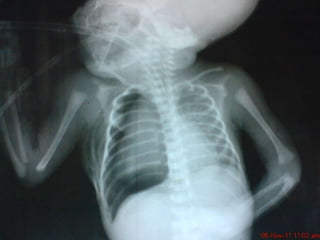

Neumotórax

• Es la presencia de aire

ectópico en el espacio

pleural

• Atelectasia pulmonar

ipsilateral

• Desplazamiento del

mediastino

contralateral

HALLAZGOS RADIOLOGICOS             HALLAZGOS GASIMETRICOS

1.   Despegamiento parietal

2.   Desplazamiento mediastínico 1.     Hipoxemia depende la

3.   Atelectasia Pulmonar               gravedad

4.   En NT a tensión puede verse   2.   Acidosis Mixta en estadios

microcaria y/o aplanamiento        tardíos

o inversión diafragmática

Neumotórax HALLAZGOS RADIOLOGICOS HALLAZGOS GASIMETRICOS 1. Despegamiento parietal 2. Desplazamiento mediastínico 1. Hipoxemia depende la 3. Atelectasia Pulmonar gravedad 4. En NT a tensión puede verse 2. Acidosis Mixta en estadios microcaria y/o aplanamiento tardíos o inversión diafragmática